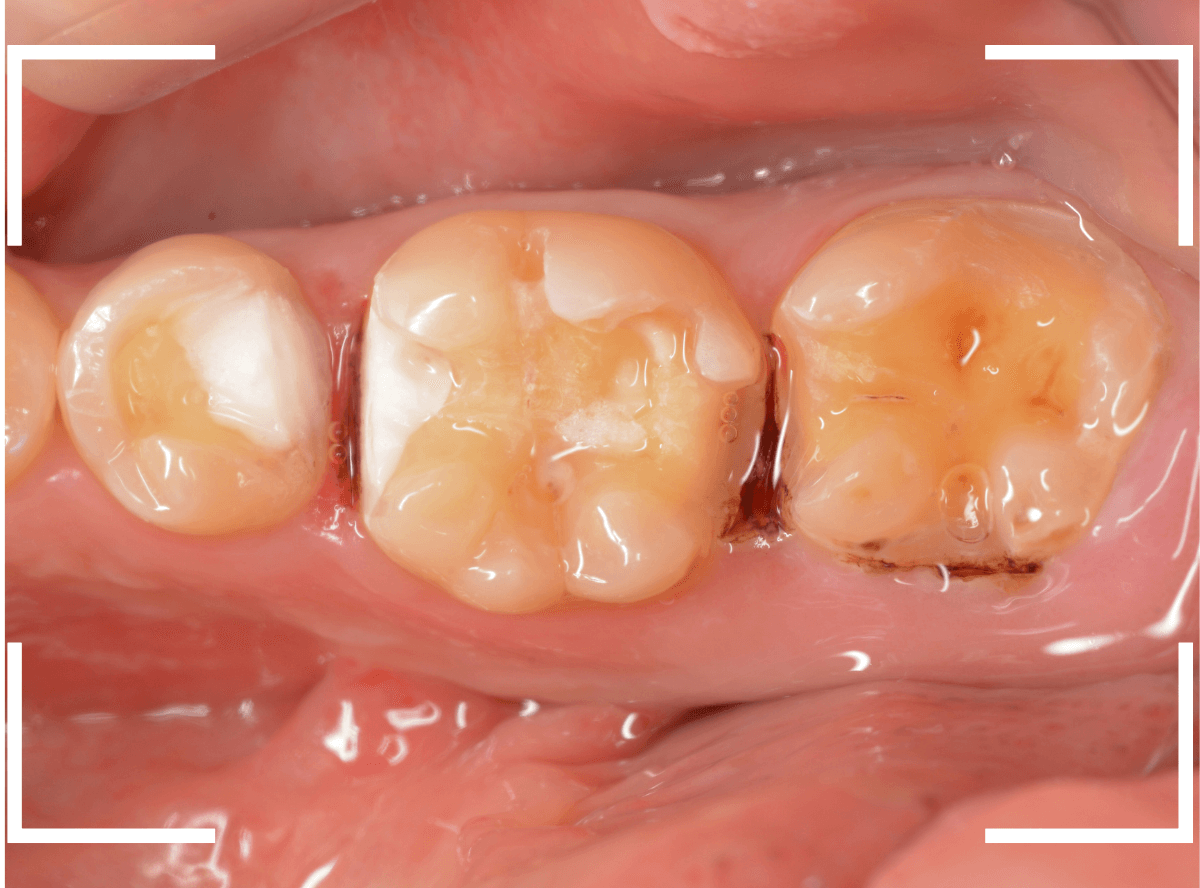

Case.28 虫歯治療後、半年以上来院されなかった患者さん

虫歯を治療して、セメントで歯を削った部分を封鎖した後、再修復を検討中で、半年以上来院されなかった患者さんです。

虫歯を治療して、セメントで封鎖した状態というのは、家でいえば、しっかりした屋根がない状態です。

今回は、セメントの一部がはがれる程度で済んでいましたが、虫歯が再発し、再治療、最終修復物の変更の可能性も出てきます。

皆さんも治療は中断せずに最後まで通院するようにしてくださいね。

治療再開後、セラミックの最終修復を希望されましたので、歯をトリミングし、型取りします。

治療後の状態です。

治療後の定期メンテナンスに来院されない患者さんもまれにいらっしゃいますが、一定期間来院のない方は破折などの際の保証も受けられません。

くれぐれも忘れずに来院していただくようにお話しし、終了となりました。